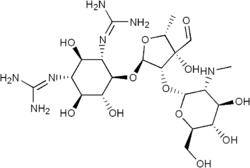

| Various pharmaceutical tuberculosis treatments and their actions | |